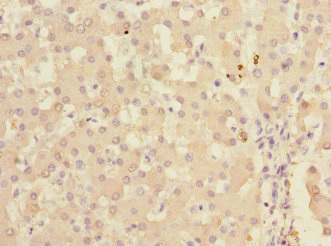

Immunohistochemistry of paraffin-embedded human liver tissue using CSB-PA012157ESR1HU at dilution of 1:100